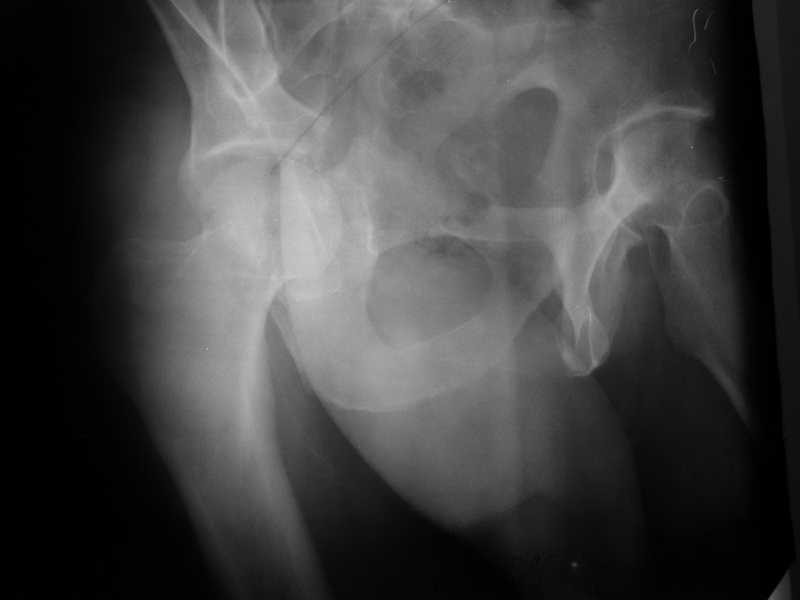

> I would like to present a case of a young (22 yo) male who suffered

> a car crush. He has combined transverse and posterior wall fracture of

> the right acetabulum as well as a nondisplaced fracture of the left

> acetabulum and bimalleolar fracture of the left ankle. Initially we did

> a combined lateral and axial traction to the right leg . The

> patient is stable now ( 6 day after the accident ), so I would like to ask for

> your opinion for the best course of treatment of the right acetabulum.

Yordan! In this case position of bone fragments is quite good. We

prefer to use miniinvasive technique. We fix posterior column by can.

screw and put 3mm pin with distal thread to the anterior column. Next day after

Вложение не в текстовом формате было извлечено…

Имя     : 2.jpg

Url     : http://weborto.net:8080/pipermail/ortho/attachments/20081205/95456be3/attachment-0004.jpg